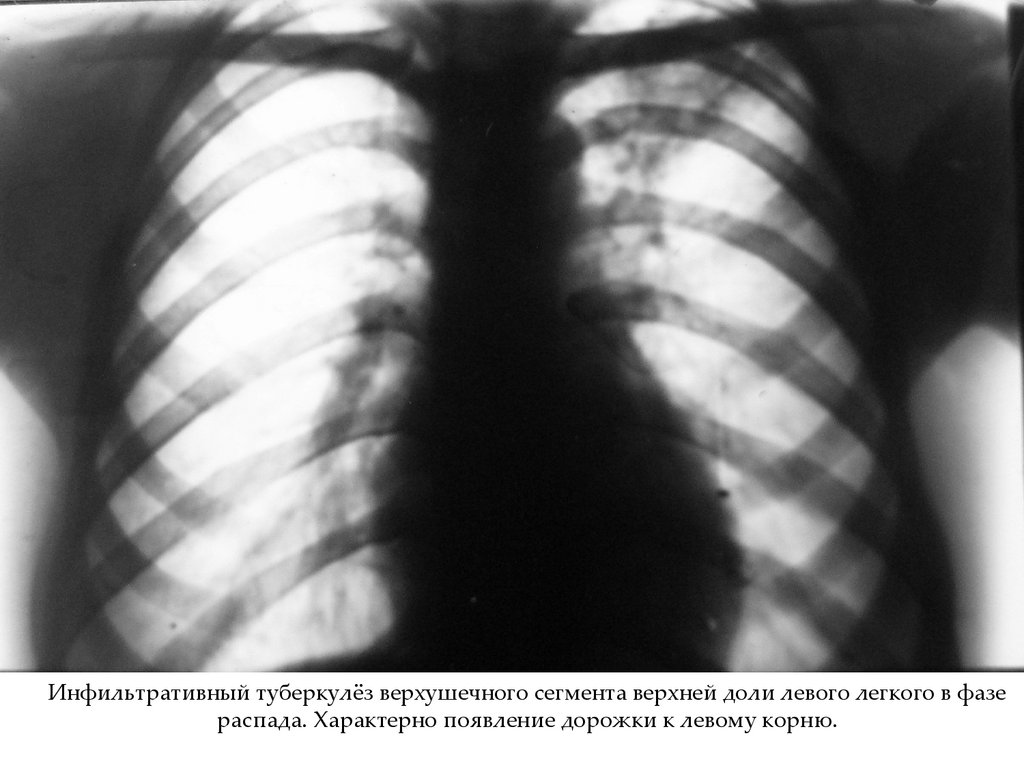

Инфильтративный туберкулёз верхушечного сегмента верхней доли левого легкого в фазе

распада. Характерно появление дорожки к левому корню.